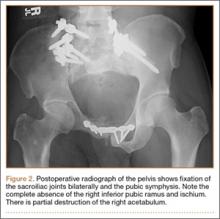

Thirty-seven months after his initial presentation, he underwent posterior spinal fusion L5 to S1, SI fusion, and anterior locking plate fixation of the pubic symphysis, as seen in Figure 2. Pathology from surgical specimens, seen at original magnification ×20 and ×100 in Figures 3A and 3B, respectively, showed prominent vascular proliferation in the right ilium, with reactive bone changes in the left ilium and right sacrum. A lytic lesion showed fibrous tissue with an embedded fragment of necrotic bone.